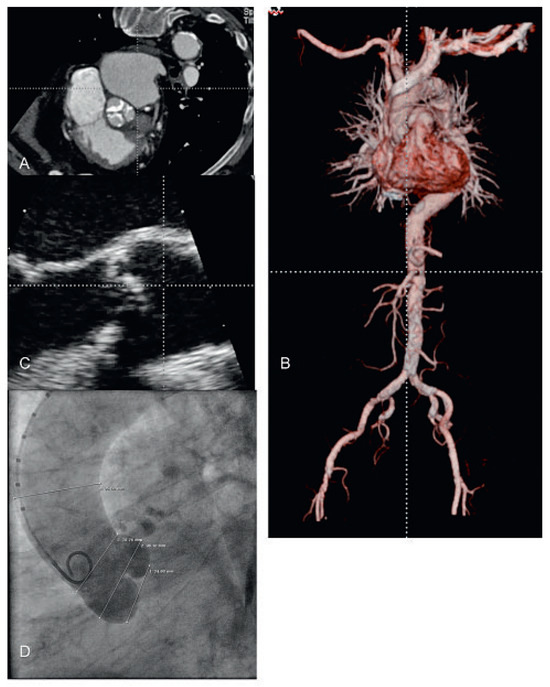

Severe calcific aortic stenosis is a disease of the elderly and associated with reduced quality of life and adverse prognosis. According to demographic estimations the share of octogenarians will markedly increase in the course of the decades to come...